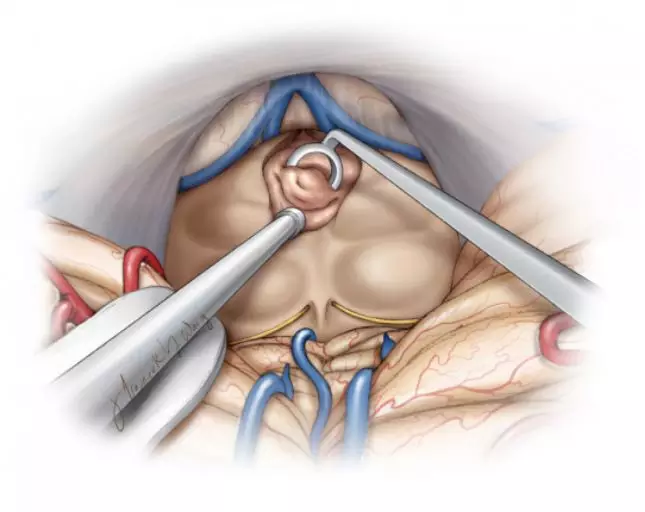

图6. 经顶盖区暴露范围有限。在这些病例中,可用环形刮匙从脑室内刮除肿瘤。

图7. 肿瘤切除结束时,可清晰看到脑内静脉和三脑室前部结构。手术盲点很多,包括顶盖前缘,刚好位于术腔“唇部”的前方。强烈推荐使用成角内镜或反光镜。盲目牵拉肿瘤可能会损伤脑室壁或相关的静脉。